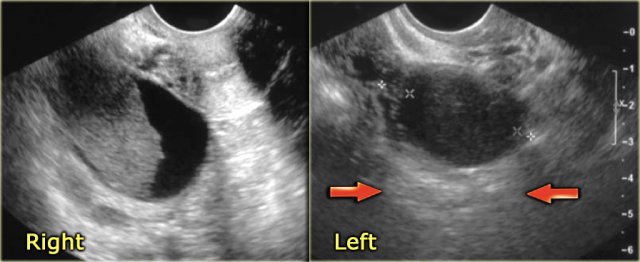

The ultrasound images show the right and left ovary: on both sides there is what appears to be a solid lesion.

There is however good through transmission, which indicates that we are probably dealing with hemorrhagic cysts.

On Doppler US (not shown) there was no vascularity.

On the axial T2-weighted image both lesions show typical 'shading'.

The gradual drop in T2 is thought to be caused by a combination of increasing viscosity and increasing concentration of protein and iron towards the dependent portion of the lesion.

There is no enhancement on the subtraction image (Post-Gd minus Pre-Gd).

Again, subtraction is useful in cases like this: Gd-induced signal increase over the already very bright pre-contrast image would be very hard to appreciate otherwise.